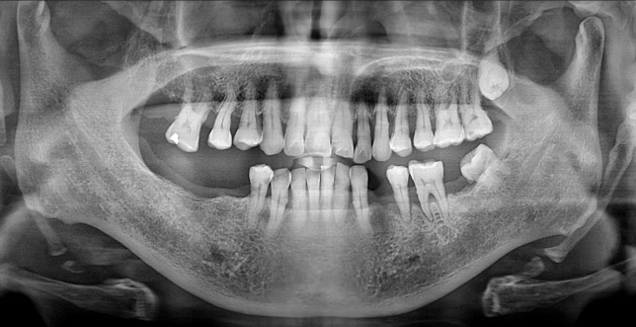

Before

위 케이스 에서는 아래 어금니가 없이 오래 계셔서 위 어금니가 내려오는 정출 현상을 확인 하실 수 있습니다.